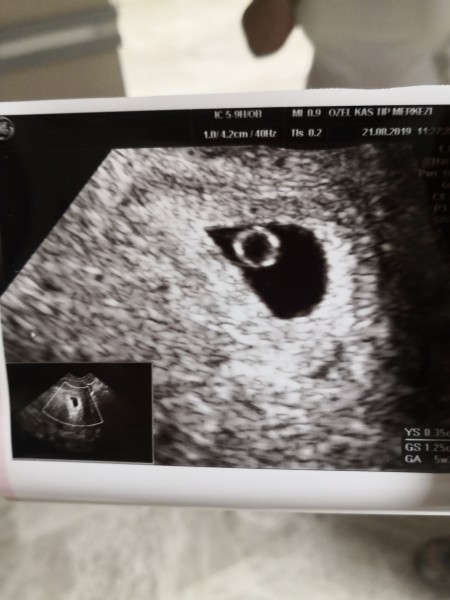

İyi akşamlar bugün doktoruma kontrole gittim normalde bugün 7.haftaya girdim son adet tarihim 20 ocak ama kalp atışlarını duyamadık kese var ama embriyo yok içinde gözükmüyor sadece halkası gözüküyordu doktor iki şeyden şüphelendi ya boş gebelik yada geç döllenme dedi perşembe günü tekrar kontrol edecek çok kötüyüm çok morelim bozuk göz yaşlarıma hakim olamıyorum ilk gebeliğim ister istemez çok üzüldüm benim gibi bu durumu yaşayan var mı acaba

image

Bak, canım uygulamalı olsun dıye gosterıyorum halka dedıgı buysa eger bu yolk sac yanı bebegın ılk 12 hafta beslencegı kese bu varsa bebek vardır ama sadece gördüğü kese ise bekletir. Ben bu yolk sacı 5+5di sanrm alttan muayne ıle gordu cunku geç döllenmeydi benıde korkutmustu boş olabilir diye gönlünü rahat tut